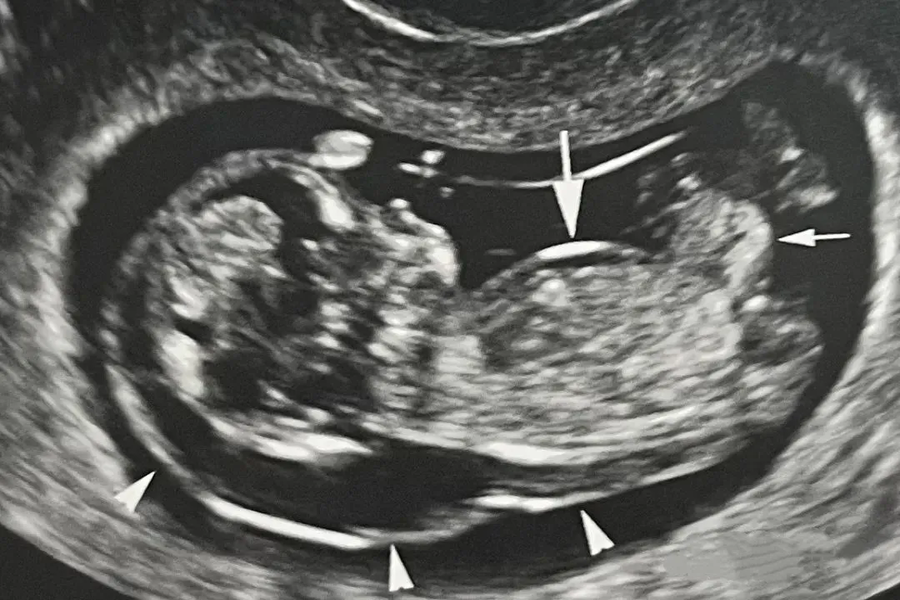

Hội chứng này có thể được sàng lọc sớm ngay trong 3 tháng đầu thai kỳ thông qua các phương pháp như xét nghiệm sàng lọc không xâm lấn qua máu mẹ, siêu âm hình thái đo độ mờ da gáy. Các trường hợp sàng lọc thai nguy cơ cao sẽ được tư vấn chẩn đoán trước sinh bằng các phương pháp sinh thiết gai nhau, chọc hút dịch ối.

Hội chứng Down được sàng lọc thông qua siêu âm hình thái, đo độ mờ da gáy ở tuần thai 11 đến 13 tuần 6 ngày

ThS. BSNT Nguyễn Đức Anh – Chuyên gia Di truyền, Trung tâm Y học Bào thai, Bệnh viện Đại học Phenikaa cho biết: “Đa số các dị tật bẩm sinh, đặc biệt là các bất thường lớn về hình thái và nhiễm sắc thể, có thể được phát hiện thông qua siêu âm đo độ mờ da gáy ở tuần 11-13 và siêu âm hình thái học 4D ở tuần 18-22. Kết hợp với các xét nghiệm như NIPT hay chẩn đoán xâm lấn nếu có chỉ định, chúng ta có thể đánh giá toàn diện các vấn đề mà thai nhi có thể gặp.”